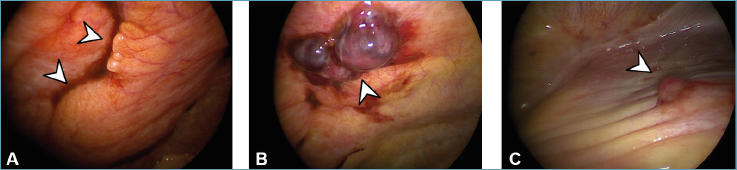

Si eseguiva la toracoscopia mediante strumentazione rigida, in sedazione profonda con propofol (100 mg), fentanil (0,1 mg) e midazolam (2 mg), associata ad anestesia locale del punto di ingresso in cavo pleurico con lidocaina 2% e mepivacaina. A livello macroscopico si evidenziava un polmone regolarmente espanso e normopigmentato. A livello della pleura parietale si visualizzavano la presenza di ipertrofia del tessuto adiposo paravertebrale, una singola formazione polipoide color porpora, quest’ultima compatibile con un coagulo in sede di pregressa toracentesi, e accumuli antracotici in prossimità del seno costo-frenico. Il diaframma risultava normoconformato con una singola piccola nodulazione (Fig. 2). Si eseguivano le biopsie rispettivamente a livello del tessuto adiposo, sulla formazione polipoide (coagulo) e a livello della nodulazione diaframmatica. Al termine della procedura si procedeva a praticare un talcaggio (STERITALC® 3g) con tecnica poudrage, con finalità di trattamento sintomatico e allo scopo di ridurre la probabilità di recidiva del versamento pleurico. La procedura si concludeva senza complicanze e con il posizionamento di un drenaggio toracico 24 fr. La radiografia post-procedura evidenziava una rapida e completa riespansione polmonare, in assenza di versamento pleurico residuale (Fig. 3A). La rimanente durata della degenza risultava regolare, il drenaggio veniva rimosso quattro giorni dopo la procedura, e il paziente veniva dimesso al domicilio sei giorni dopo la procedura stessa.

Figura 2.Immagini endoscopiche. A: ipertrofia del tessuto adiposo (freccia) a livello della pleura parietale. B: coagulo (freccia) confermato istologicamente in sede di pregresso accesso al cavo pleurico da parte di ago da toracentesi. C: nodulazione diaframmatica (freccia).